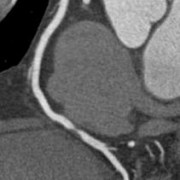

RCA

RCA-Stenose

Eine CT-Angiographie kann insbesondere sinnvoll sein bei Patienten ohne bekannte KHK mit unklarem Brustschmerz oder Atemnot, bei denen EKG-Untersuchungen, Echokardiographie und Bluttests keinen eindeutigen Hinweis auf eine Einengung der Herzkranzgefäße gezeigt haben. Die CT-A kann, auf der Basis unserer modernen CT-Technologie, die Herzkranzarterien hochaufgelöst und trotz schlagenden Herzens bewegungsfrei darstellen, so dass es uns Ärzten möglich ist, nicht nur Gefäßverschlüsse, sondern auch den Schweregrad einer Gefäßeinengung zu detektieren. Hieraus ergibt sich eine mögliche Aussage über die Notwendigkeit einer invasiven Herzkatheteruntersuchung bei einem Kardiologen zur weiteren Abklärung bzw. Behandlung des im CT erhobenen Befundes. Somit können durch die Herz-CT-Untersuchung unnötige invasive Herzkatheteruntersuchungen bei Patienten verringert werden.

Insgesamt besteht eine Einschränkung der Aussagekraft der CT-A bei sehr stark verkalkten Herzkranzarterien. Daher machen wir in unserer Praxis vor der eigentlichen CT-Angiographie immer einen nativen CT-Scan für den Kalk-Nachweis, um Patienten mit einer ausgeprägten Konorasklerose herauszufiltern und ihnen einen unnötige Kontrastmittelgabe zu ersparen. Solche Patienten sollten im Umkehrschluss zur weiteren Abklärung einer Herzkatheteruntersuchung zugeführt werden.